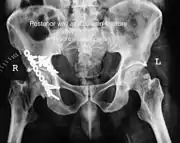

Transverse fracture showing upper iliac fragment, lower ischial and pubic fragment

Transverse fracture fixed with screws and plate

| Transverse | In this variety of fracture, the innominate bone is broken such that the upper part consists of ilium with weight bearing dome and the lower part consists of ischium and pubic bones. It typically occurs when the injuring force is applied from the side, against the greater trochanter of the femur bone, as in a fall on the side or being hit on the side. This is a two part fracture, but though both columns are broken, it is not a true both-column fracture, as the weight bearing dome is still attached to main ilium.

In this variety of fracture, the innominate bone is broken such that the upper part consists of ilium with weight bearing dome and the lower part consists of ischium and pubic bones. It typically occurs when the injuring force is applied from the side, against the greater trochanter of the femur bone, as in a fall on the side or being hit on the side. This is a two part fracture, but though both columns are broken, it is not a true both-column fracture, as the weight bearing dome is still attached to main ilium. Depending on the level at which the fracture line passes in relation to weight bearing area, the transverse fracture is further subdivided into types:

X-ray visualization is best done in Antero posterior view and Iliac and obturator oblique views. In CT scan the characteristic feature is that the fracture line runs from front to back. CT scan also helps in identifying impaction of bone pieces and if there are pieces in the joint |